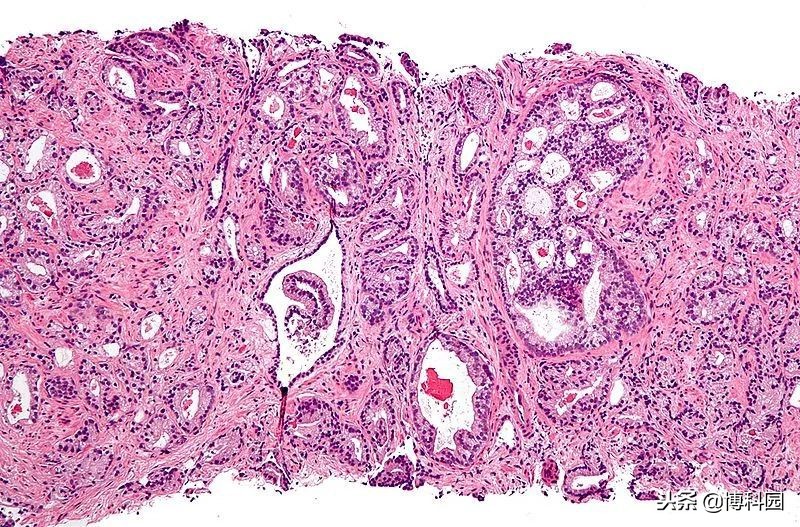

前列腺腺泡腺癌(最常见的前列腺癌)的显微照片,图片:Wikipedia